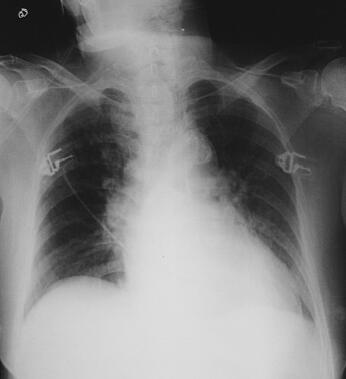

辅助检查:便常规和便潜血未见异常;胸片:心肺膈未见明显异常(图1)。心电图:室上性心动过速、偶发交界性期前收缩(图2)。

图1 入院时胸片